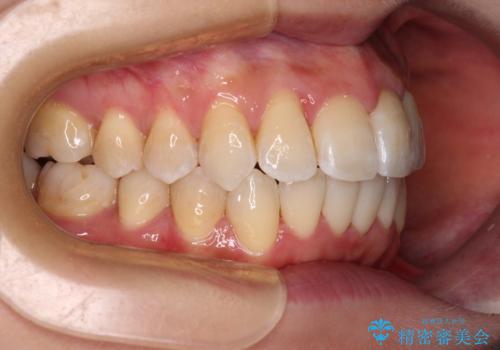

1. 【モニター】急速拡大装置 狭い歯列を拡大してワイヤー装置で短期間治療の治療前